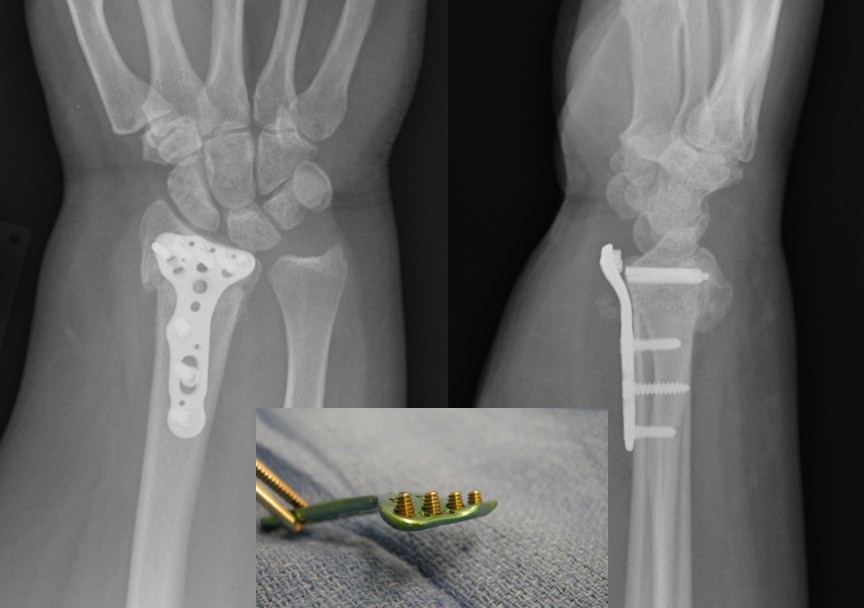

From www.injuryjournal.com

Complications after volar locking plate fixation of distal radius Radius Failure Reason  I'm working with a laptop windows 11 that is unable to authenticate when attempting to establish a wireless connection with eap (peap). To test the radius object and see if this is working properly, use the following cli command: This article addresses troubleshooting all issues that have to do with radius authentication and accounting. Num_eap ='x' means the authentication failed. Radius Failure Reason.